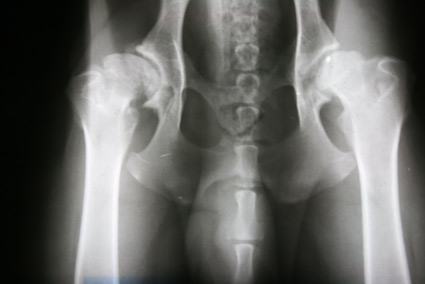

![]() HD fast-normal / HD-B / HD-1 |

B |

= Übergangsform |

HD-1 |

fast-normal |

Fast normal, geringe Veränderungen an Kopf oder Pfanne, NORBERG-Winkel von mindestens 100 Grad |